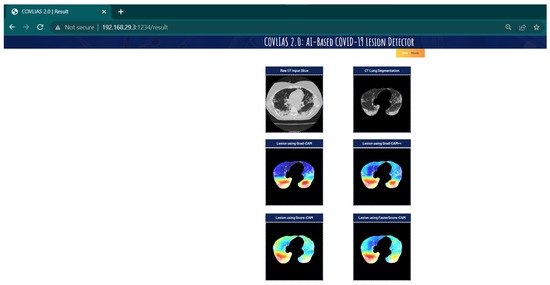

Visual Results Representing Lesion Using the Four CAM Techniques